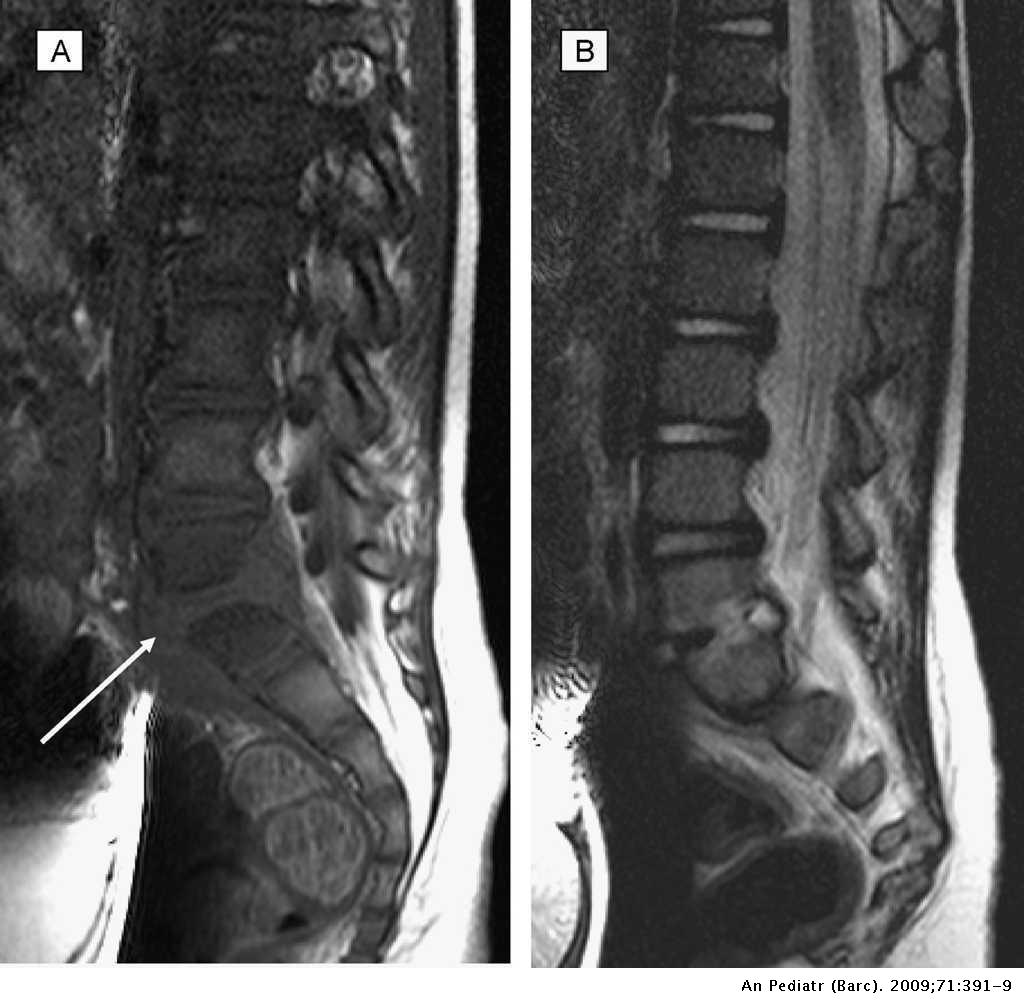

Espondilodiscitis diagnóstico y seguimiento a mediolargo plazo de 18 casos Anales de Pediatría